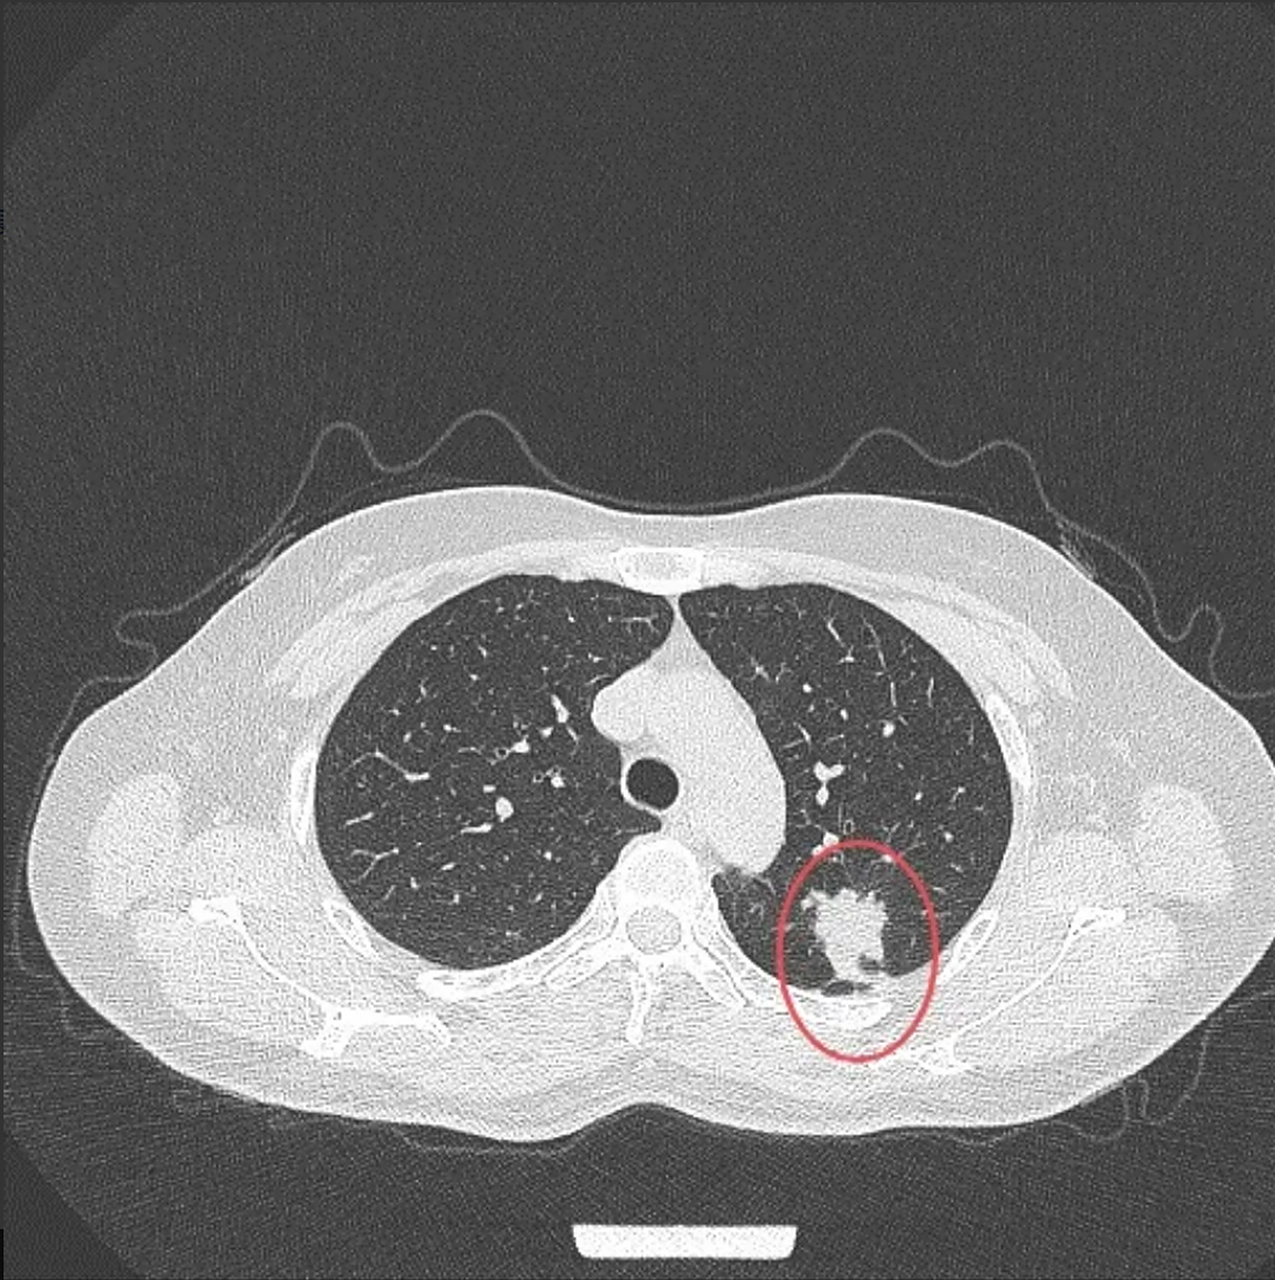

8厘米肺癌,4枚淋巴结转移 这位女士50多岁,不抽烟, 因为胸疼做ct检查

图片尺寸1275x1280